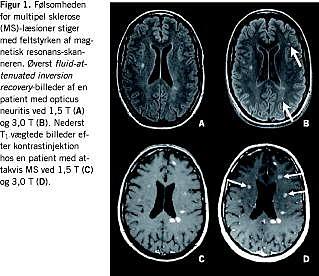

En lang række faktorer kan ændre følsomheden for MS-læsioner ved MR-skanninger, herunder feltstyrken af skanneren (Figur 1). I tilfælde af få læsioner kan dette få betydning for det påviste antal læsioner og dermed for disseminering i sted og tid - og i sidste ende diagnosen [5]. Der anbefales anvendelse af feltstyrker på mindst 1,5 T, for at man kan se mindre læsioner [6], og det anbefales, at eventuelle opfølgningsskanninger foretages med samme feltstyrke som den initiale. Der skal dog ikke opstilles rigide krav til feltstyrken, da skannere med høj feltstyrke bliver stadig mere udbredte, og MR-skanning med lav feltstyrke er bedre end ingen skanning.